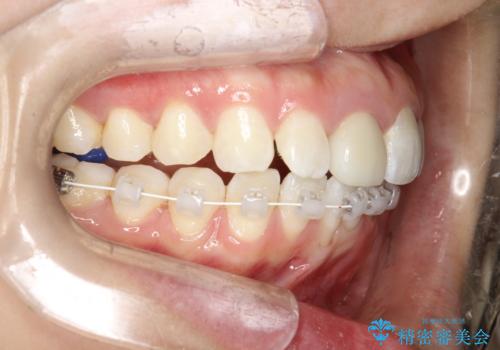

- 矯正装置

- ワイヤー(ハーフリンガル)

- ワイヤーで矯正した後戻りをマウスピースで治そうとしたが、使えなかったため再度ワイヤー矯正希望で来院されました。

装置はハーフリンガルを選択しています。

矯正としてはマウスピースでできましたが、患者さんの希望でワイヤー(ハーフリンガル)で矯正を行いました。

右下1が歯肉退縮していたため、アーチを拡げないように歯と歯の間を削って隙間をあけて並べています。